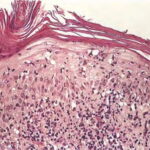

HISTOPATHOLOGY As with the morphology of the clinical lesions, pityriasis lichenoides can exhibit a range of histopathologic features encompassing acute, chronic, and intermediate lesional variants . All cases of pityriasis lichenoides contain an interface dermatitis that is denser and more wedge shaped in the acute lesions. The infiltrate is composed mainly of lymphocytes with a variable admixture of neutrophils and histiocytes. There is exocytosis, parakeratosis, and extravasation of erythrocytes. Epidermal damage ranges from intercellular and extracellular edema in less severe cases to extensive keratinocyte necrosis, vesicles, pustules, and ulcers. The acute variants can exhibit lymphocytic vasculitis with fibrinoid degeneration of blood vessel walls. Occasional CD30+ lymphoid cells and occasional atypical lymphoid cells may be seen as a non-specific finding in many cutaneous lymphoid infiltrates. The presence of an appreciable numbers of these cells is not consistent with classic pityriasis lichenoides of any type and should raise concern for the lymphomatoid papulosis-CD30+ anaplastic large cell lymphoma disease spectrum.74 Other immunohistologic features and the clonality of pityriasis lichenoides are discussed in Etiology and Pathogenesis. Differential Diagnosis The differential diagnosis of pityriasis lichenoides includes many papular eruptions . Those that develop crusts, vesicles, pustules, or ulcers are grouped with PLEVA, whereas those that form predominantly scaly papules are grouped with PLC. Most of them can be excluded based on history and typical clinicopathologic features. A few, such as secondary syphilis and viral-associated lesions, also can be excluded based on serologic tests. Among the most challenging diseases to distinguish from pityriasis lichenoides are lymphomatoid papulosis and macular or papular variants of MF. As detailed earlier, the presence of large atypical lymphoid cells (often CD30+) differentiates lymphomatoid papulosis from pityriasis lichenoides.Macular or papular variants of MF are rare. They exhibit classic features of MF, including small atypical epidermotropic lymphoid cells with convoluted nuclei and a band-like superficial dermal lymphoid infiltrate. Complications Secondary infection is the most common complication of pityriasis lichenoides. PLEVA may be associated with low-grade fever, malaise, headache, and arthralgia. Patients with PLUH can develop high fever, malaise, myalgia, arthralgia, and gastrointestinal and central nervous system symptoms. Occasionally, debilitated patients may die. PLC has been associated uncommonly with LPP in children. Despite